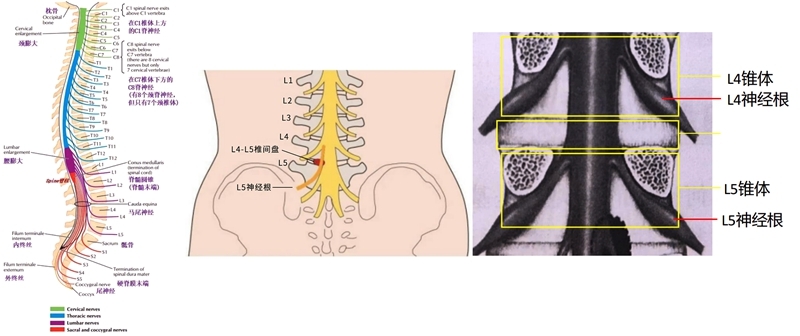

L5神经根解剖

L5神经根是腰椎间盘突出常常累及的神经根。尤其是腰4/5节段的椎间盘突出。临床可从肌力检查、感觉检查及反射检查三个方面来判断L5神经根定位的主要标志性表现。

肌力检查:

伸踇长肌(腓深神经):检查者一手固定足跟,另一手拇指放到患者踇趾甲床上,令患者背屈踇趾,检查者用力下压抵抗背屈。外加的对抗在趾间关节近端,则检查的是伸踇长肌和伸踇短肌。如果外加的对抗在趾间关节的远侧,则仅为伸踇长肌。

伸趾长、短肌(腓深神经):令患者伸直足趾,检查者拇指在趾背侧对抗,并试图向足底弯曲足趾。正常时,足趾不会被弯曲。

臀中肌(臀上皮神经):检查臀中肌,令患者侧卧,外展大腿,并施加对抗。

L5神经根定位的主要标志性表现之“足下垂”

相关解剖

周围神经病变:L5神经根、坐骨神经、腓总神经、腓深神经、腓浅神经。